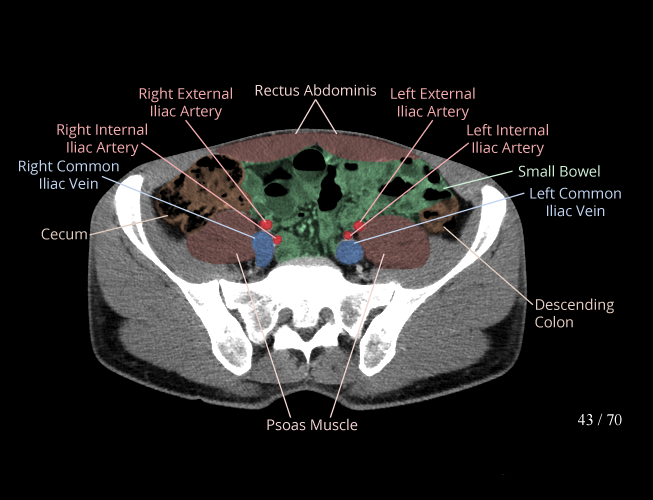

Body

Covers abdominal CT anatomy.

Pelvis

Covers pelvic MRI anatomy.